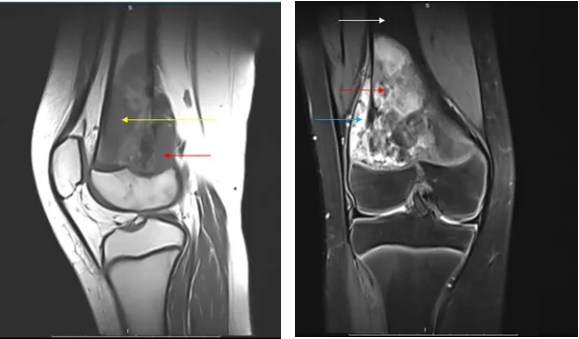

2024 年,17 岁的少年陈捷(化名)因右腿持续疼痛就医,MRI 检查显示股骨下端巨大占位,活检确诊为高度恶性骨肉瘤。更令人揪心的是,肺部 CT 发现双肺散在分布 12 枚转移灶,最大直径达 2.5 厘米 —— 这意味着肿瘤已进入晚期,传统治疗手段预后极差。